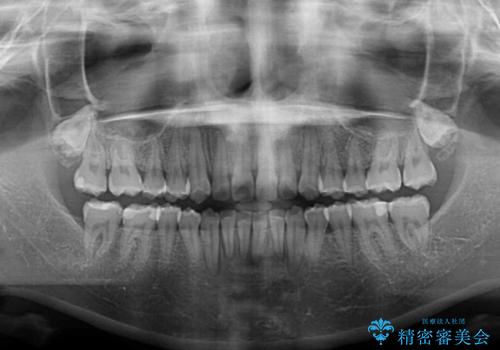

- デコボコを気にして来院された患者様です。

インビザラインでもワイヤー装置でも対応可能でしたが、自己管理の煩わしさの観点から、楽して治療のできるワイヤー装置を選択されました。

抜歯するほどではないものの、やや口元の突出感が気になっていたので、補助装置により上顎臼歯を後方に移動させることで、突出感改善を図ることとしました。

1年弱の短期間で、望み通りのスッキリとした口元に仕上げることができました。